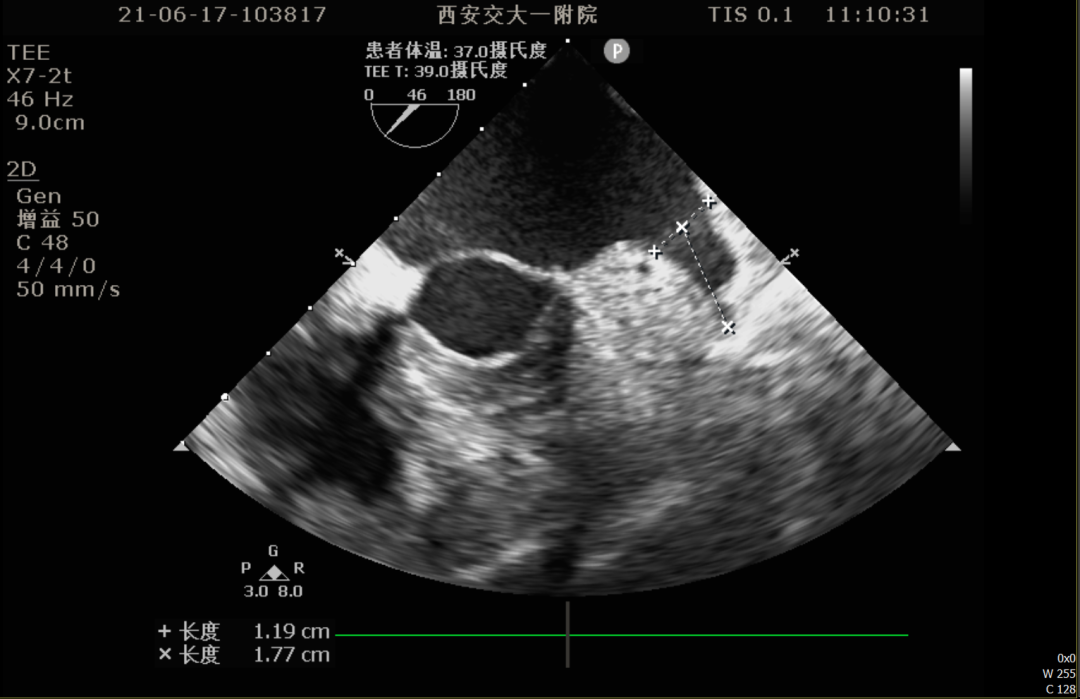

86°TEE

TEE测量左心耳数据:

TEE测量结果:

该患者左心耳开口较小,呈反鸡翅型,开口处即反折,同时内部梳状肌发达,且深度较浅,因此手术难度偏大,术前安排进一步CT评估以协助制定手术策略。